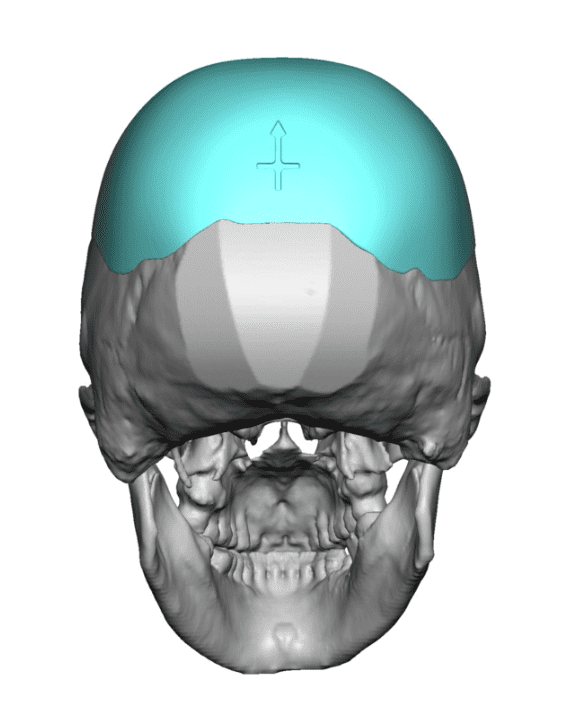

Desire for a higher and more prominent crown of the skull.

Crown of skull augmentation using a custom skull implant.

Desire for a higher and more prominent crown of the skull.

Crown of skull augmentation using a custom skull implant.